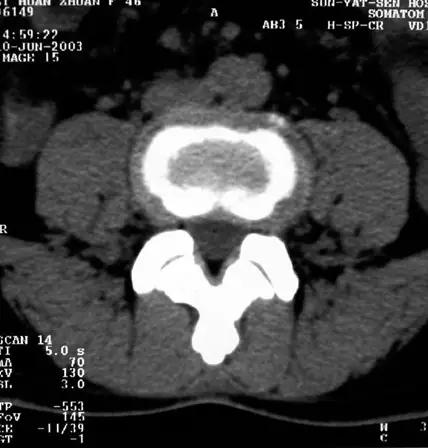

椎间盘脱出伴髓核游离

椎间盘脱出